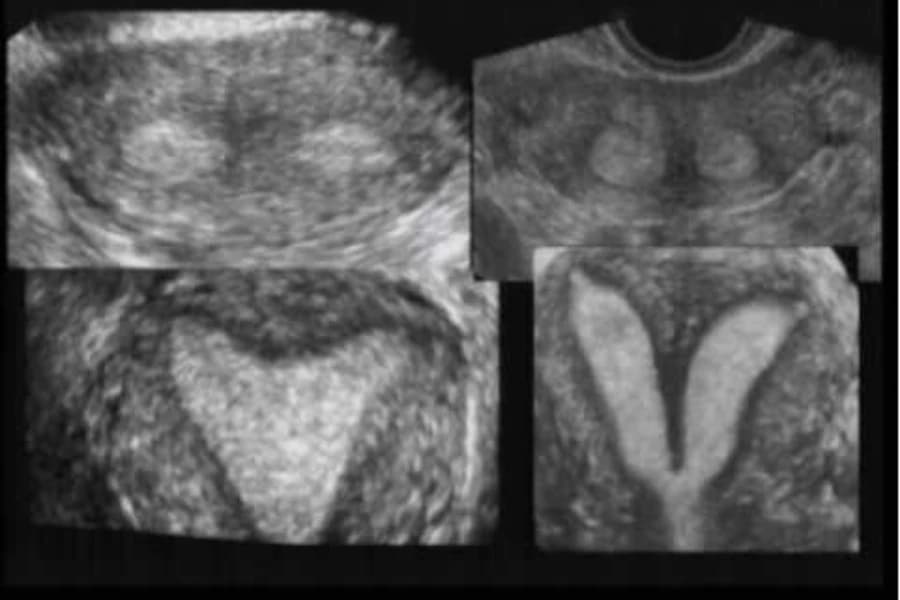

Ghi nhận hai trường hợp trẻ có tử cung đôi

GD&TĐ - Bệnh viện Sản Nhi Nghệ An cho biết, trong vòng một tháng, đơn vị đã tiếp nhận và điều trị thành công hai trường hợp mắc hội chứng hiếm gặp...